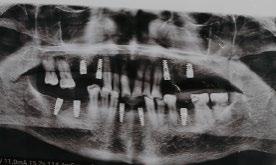

• Estudios radiográficos (ortopantomografía):

Se observa el órgano dentario 33 retenido de manera transversal con un botón de ortodoncia colocado como alternativa durante el anterior tratamiento (Figura 2).

Paciente femenina de 30 años de edad que acude a consulta privada para segunda valoración ortodóntica debido a un mal tratamiento llevado a cabo en otro sector privado (Figura 1). Tras una correcta anamnesis y valoración, se realizó la propuesta de tratamiento de un trasplante dental, considerando que la paciente cumple con las características clínicas y biológicas requeridas para dicho procedimiento (Figura 2).